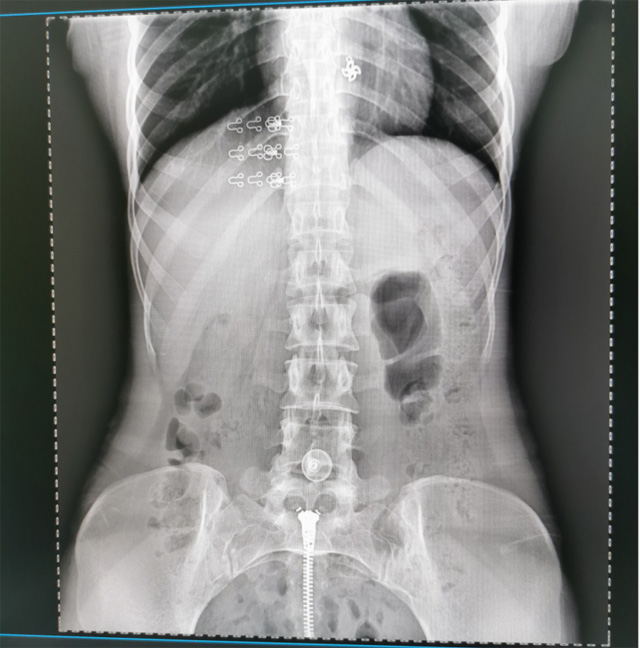

提高醫院的影像科的醫療服務水平,滿足滿足人民群眾不斷增長的醫療需求,促進醫療技術快速發展。醫院都引進懸吊DR拍片設備新一代數字化X線攝影系統。標志著醫院的診療水平又上升一個新的臺階。懸吊DR滿足人體頭部、胸部、腹部、腰椎、四肢等部位的數字攝影檢查,可以檢查呼吸系統疾病,心臟系統的疾病、骨關節系統的疾病,子宮輸卵管造影、胃腸道造影,.有職業病體檢篩查塵肺病功能。通過DR數字化攝影,分段連續、重疊采集數字化圖像,利用軟件對圖像進行拼接的方式來獲得全脊柱、全上肢或全下肢的圖像。新設備的圖像更清晰,臨床拍攝避免患者再次搬運和移動產生的痛苦,是創傷骨折患者的福音。輻射減少受照劑量50%,后處理能力強、圖像質量高。有效降低操作難度,縮短工作流程,尤其適合大批量體檢。

具有射線劑量小、圖像清晰度高、誤差小等特點,懸吊DR已廣泛應用于各級醫療機構的體檢中心,越來越受到臨床醫生的肯定和患者的青睞。為臨床診斷工作提供更加直觀有效的技術支持,大大提高了患者就醫效率從而為患者提供更加優質的醫療服務。提高了其成像質量和臨床應用價值,并極大減少了受照輻射劑量。有效滿足了各種常見疾病的臨床診斷和治療需求。以醫療質量為根本,以優質服務為導向,竭誠為人民群眾的健康保駕護航。